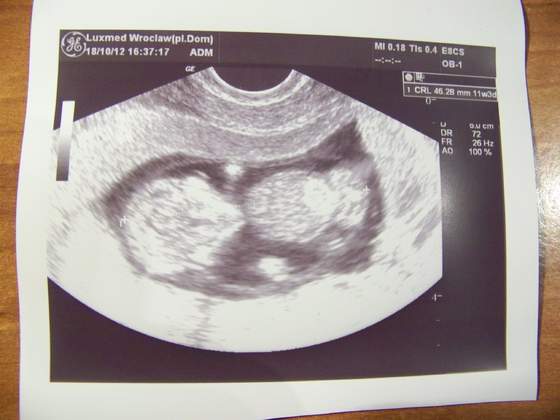

Dołączam zdjęcie mojego 4,5 cm szczęścia.